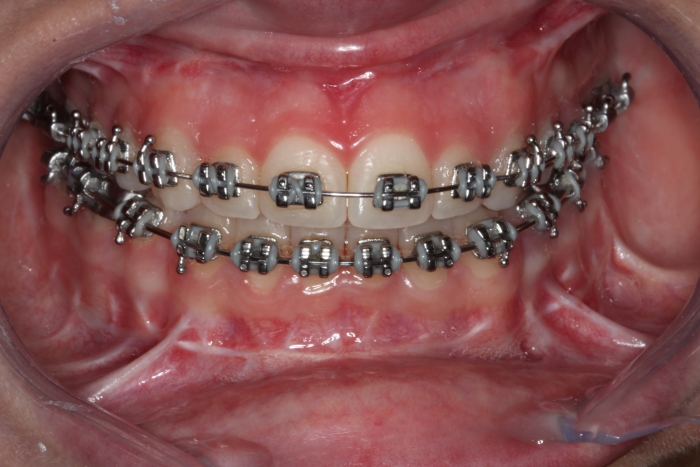

Mordida inicial

Mordida após a cirurgia